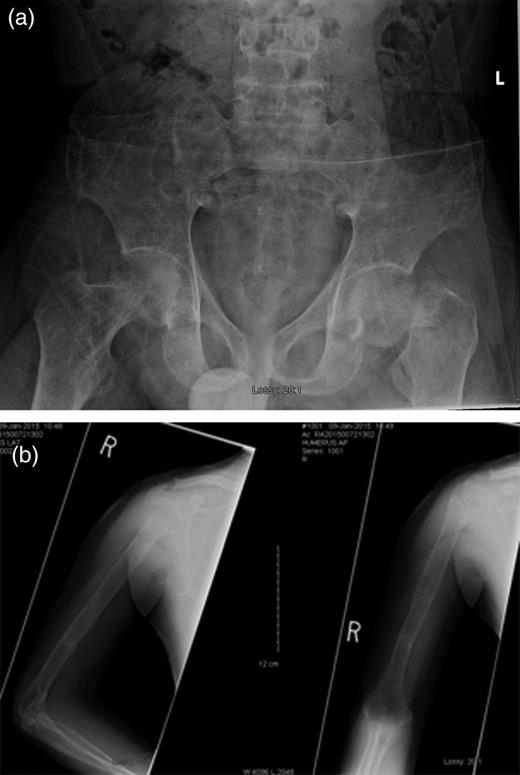

A 22-year-old male student presented to our hospital with a 2-year history of progressive lower extremity weakness. One year prior to the admission, he had been seen at another medical clinic because of fatigue and difficulty walking. His radiographs showed no fractures, and he was referred to physiotherapy for muscle strengthening. He underwent 5 months of physiotherapy. Given the lack of progress, his therapist advised him to be reassessed medically. This time, he presented to the Family Medicine clinic at our hospital. Further questioning revealed that, despite physiotherapy, his weakness had progressed and he had to quit school as he was having considerable difficulty walking up a flight of stairs. A thorough investigation was performed and showed a serum calcium level of 3.46 mmol/l (normal: 2.1–2.6 mmol/l) and a PTH level of 138 pmol/l (normal: 1.6–9.3 pmol/l). A parathyroid scan revealed a parathyroid adenoma. He was referred to our General Surgery service where he was admitted for excision of the parathyroid adenoma. Upon admission, radiographs of his pelvis showed no fracture, but severe osteopenia was observed. One day prior to the scheduled parathyroidectomy, he had a simple, low-energy fall while he was walking on his own to the hospital. Radiographs revealed a displaced subcapital fracture of his left hip, a segmental fracture of his right humerus and extreme osteopenia (Fig. 1).

(a) Left femoral neck displaced subcapital fracture and (b) right humeral shaft segmental fracture.